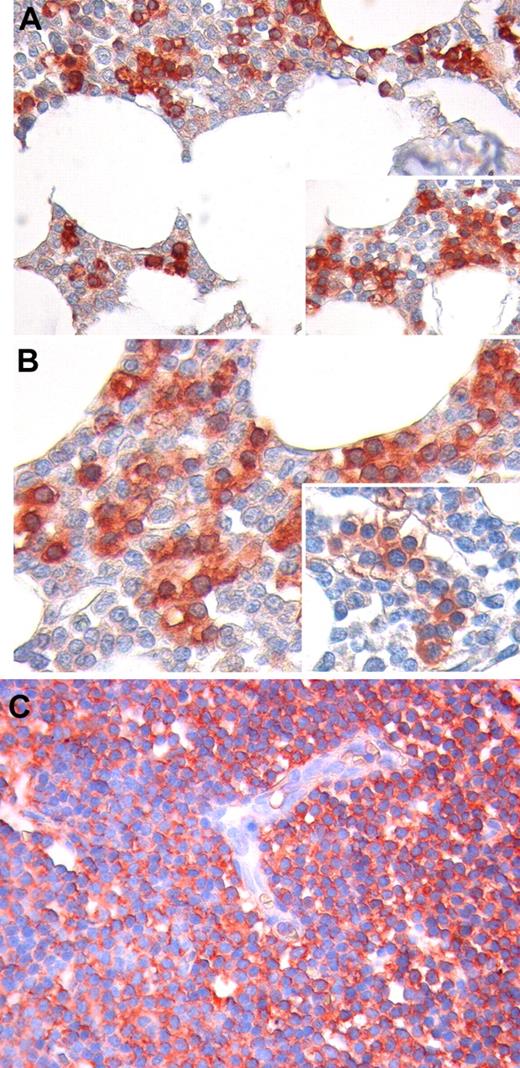

We analyzed Ang2 expression by immunohistochemistry in CLL-infiltrated BM and LN biopsies of 8 patients. In the BM compartment, we found that Ang2 staining is mainly confined to marrow infiltrating leukemic cells (Figure 4A-B). Notably, Ang2 expression was also observed in CLL cells with BM intravascular distribution. In contrast, the other BM hematopoietic cells, as well as stromal and endothelial cells, were mostly negative or slightly reactive. Similarly to BM infiltrates, neoplastic cells diffusely effacing LN architecture displayed a clear positivity to Ang2, and such a reactivity did not involve endothelia (Figure 4C).

Immunohistochemical staining for Ang2 protein in BM and LN biopsies. In BM, Ang2 immunoreactivity is mainly confined to infiltrating CLL cells (red), whereas other hematopoietic cells are mostly negative or slightly reactive (light pink; A-B). Notably, Ang2 expression is detected also in CLL cells displaying an intravascular distribution. No significant staining for Ang2 is observed on stromal and endothelial cells (A-B insets). Neoplastic cells diffusely effacing LN architecture display a clear positivity to Ang2, and such a reactivity does not involve endothelia (C). Original magnification, 200× for panels A and C, 400× for panel B.